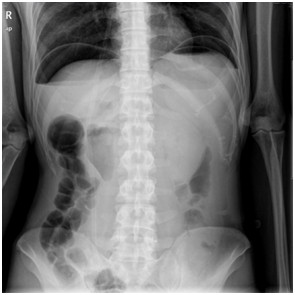

05卷-5.某急腹癥患者,其腹平片提示(本題滿(mǎn)分2.00分)

本題答案:C

【該題針對(duì)“ X線-消化道穿孔 ”知識(shí)點(diǎn)進(jìn)行考核】